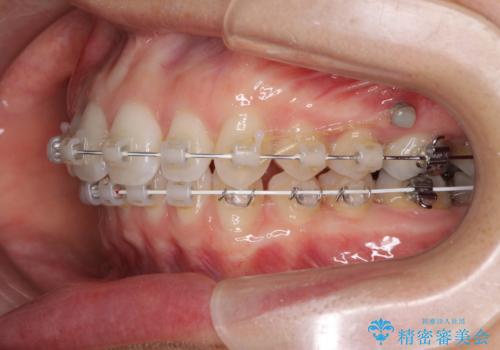

上顎歯列が、下顎に対して前方にありましたが、口元に出っ歯の印象がなかったため、親知らずを抜歯した上で、上顎歯列全体を後方に移動させることとしました。

咬合力が強いため、アンカースクリューを使用し、ワイヤー装置にて矯正治療を行うこととしました。

上顎歯列を下顎に対して4mmほど移動させる必要があったため、治療は長期化することが予想されましたが、患者様にはこちらの期待以上にゴムかけなどに協力いただき、補綴治療も含めて2年強で終えることができました。